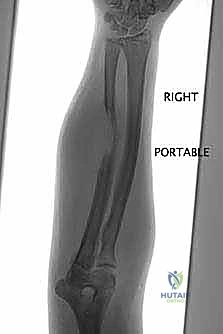

"First, we gather all our intelligence. This involves a multi-modality imaging approach. We start with plain radiographs – AP and lateral views are crucial. Look closely at the bone geometry, the exact size of the lesion, and critically, the remaining host bone stock. We need to assess its quality and quantity to ensure it can adequately support our planned reconstruction, whether it's an allograft or an endoprosthesis. Remember, inadequate bone stock means we must convert to a joint-replacing reconstruction, so this assessment is non-negotiable. Radiographs also give us our initial templating parameters for allograft sizing.

Here we see a preoperative AP radiograph, clearly delineating a diaphyseal lesion in the femur. This is our starting point for understanding the extent of bone involvement.